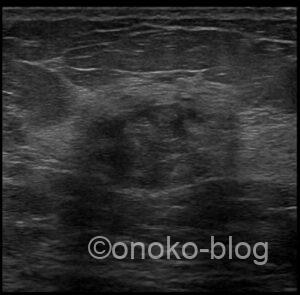

低エコー…域?腫瘤?

ここだけ乳腺が厚めだし、テクスチャーが周りと違うんですよね…

しっかり腫瘤形成してます!な感じではないような…

でも、うーん…分葉状にも見えるような…